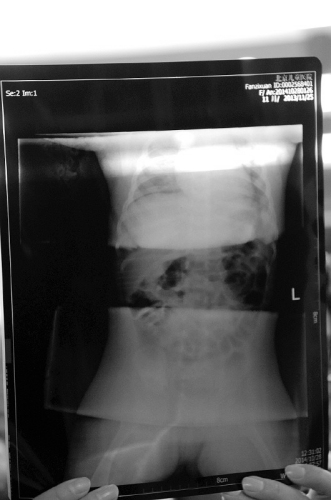

手术结束后,医院立刻为小子萱拍了一张片子,显示小子萱体内12根针已经全部被取出,且无任何残留。张学军还介绍,这12根针中有10根是注射器针头,两根是普通的缝衣针。此前,刘玉香说自己在子萱大腿处拔出过空心的医用针头。